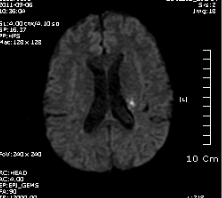

좌측사진은 PCA 영역. 우측사진은  AchA 영역의 post. periventricular corona radiata (Stroke 4ed p199, Fig 9-3 과 동일)

진행하였다면 우선 DWI follow up  중요합니다. 아마도 corona radiata 영역이 진행한 것 같지만요..

DWI coronal or saggital view 보면 분명하겠지만 이 사진으로 보니 PCA territory infarction으로 모두 설명되는 것 같습니다. PCA 영역에 hypoperfusion으로 병변이 크지는 것 같습니다. 5-7일 지나야 안정기에 들어갈 것 같습니다.